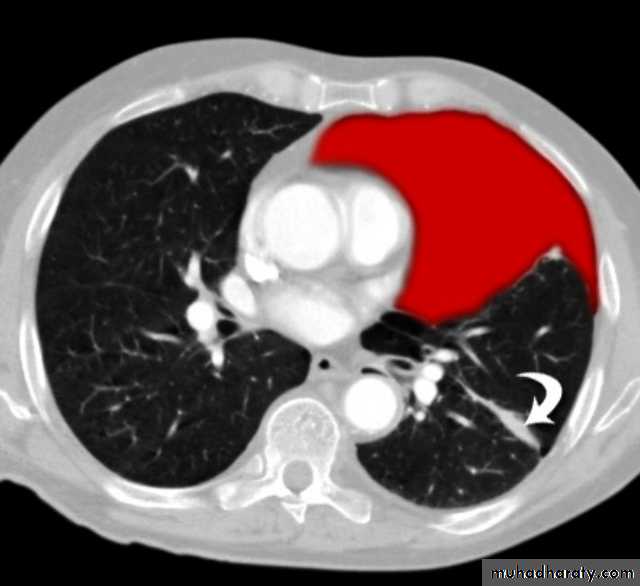

Hydatid cystAppear as large oval hypo dense area density of fluid with well defined margin , sometime at their periphery multiple flecks of calcification are seen at their periphery .

Hydatid cyst with daughter cyst , appear as multiple hypo densities rounded area within the main loculi with multiple rim of

calcification

Hydatid cyst within the liver